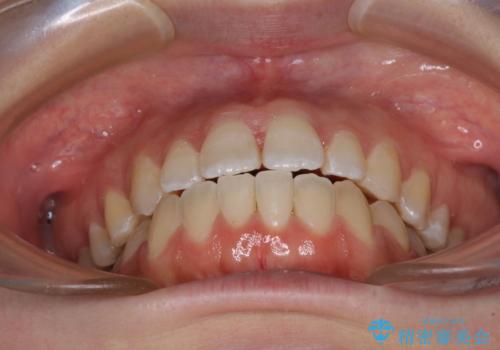

【モニター】オープンバイトをインビザラインで矯正治療

- 前歯の上下スペースによる食べにくさを気にして来院された患者様です。

インビザラインにより上下の前歯の隙間を閉じていくこととしました。

前歯のデコボコの解消と並行して上下の奥歯を圧下させるようにすることで、前歯を接触させるように計画しました。

上下の隙間に舌が入り込むことがオープンバイトの原因であったため、舌の筋肉のトレーニングも並行して行い、後戻りの抑制を図りました。